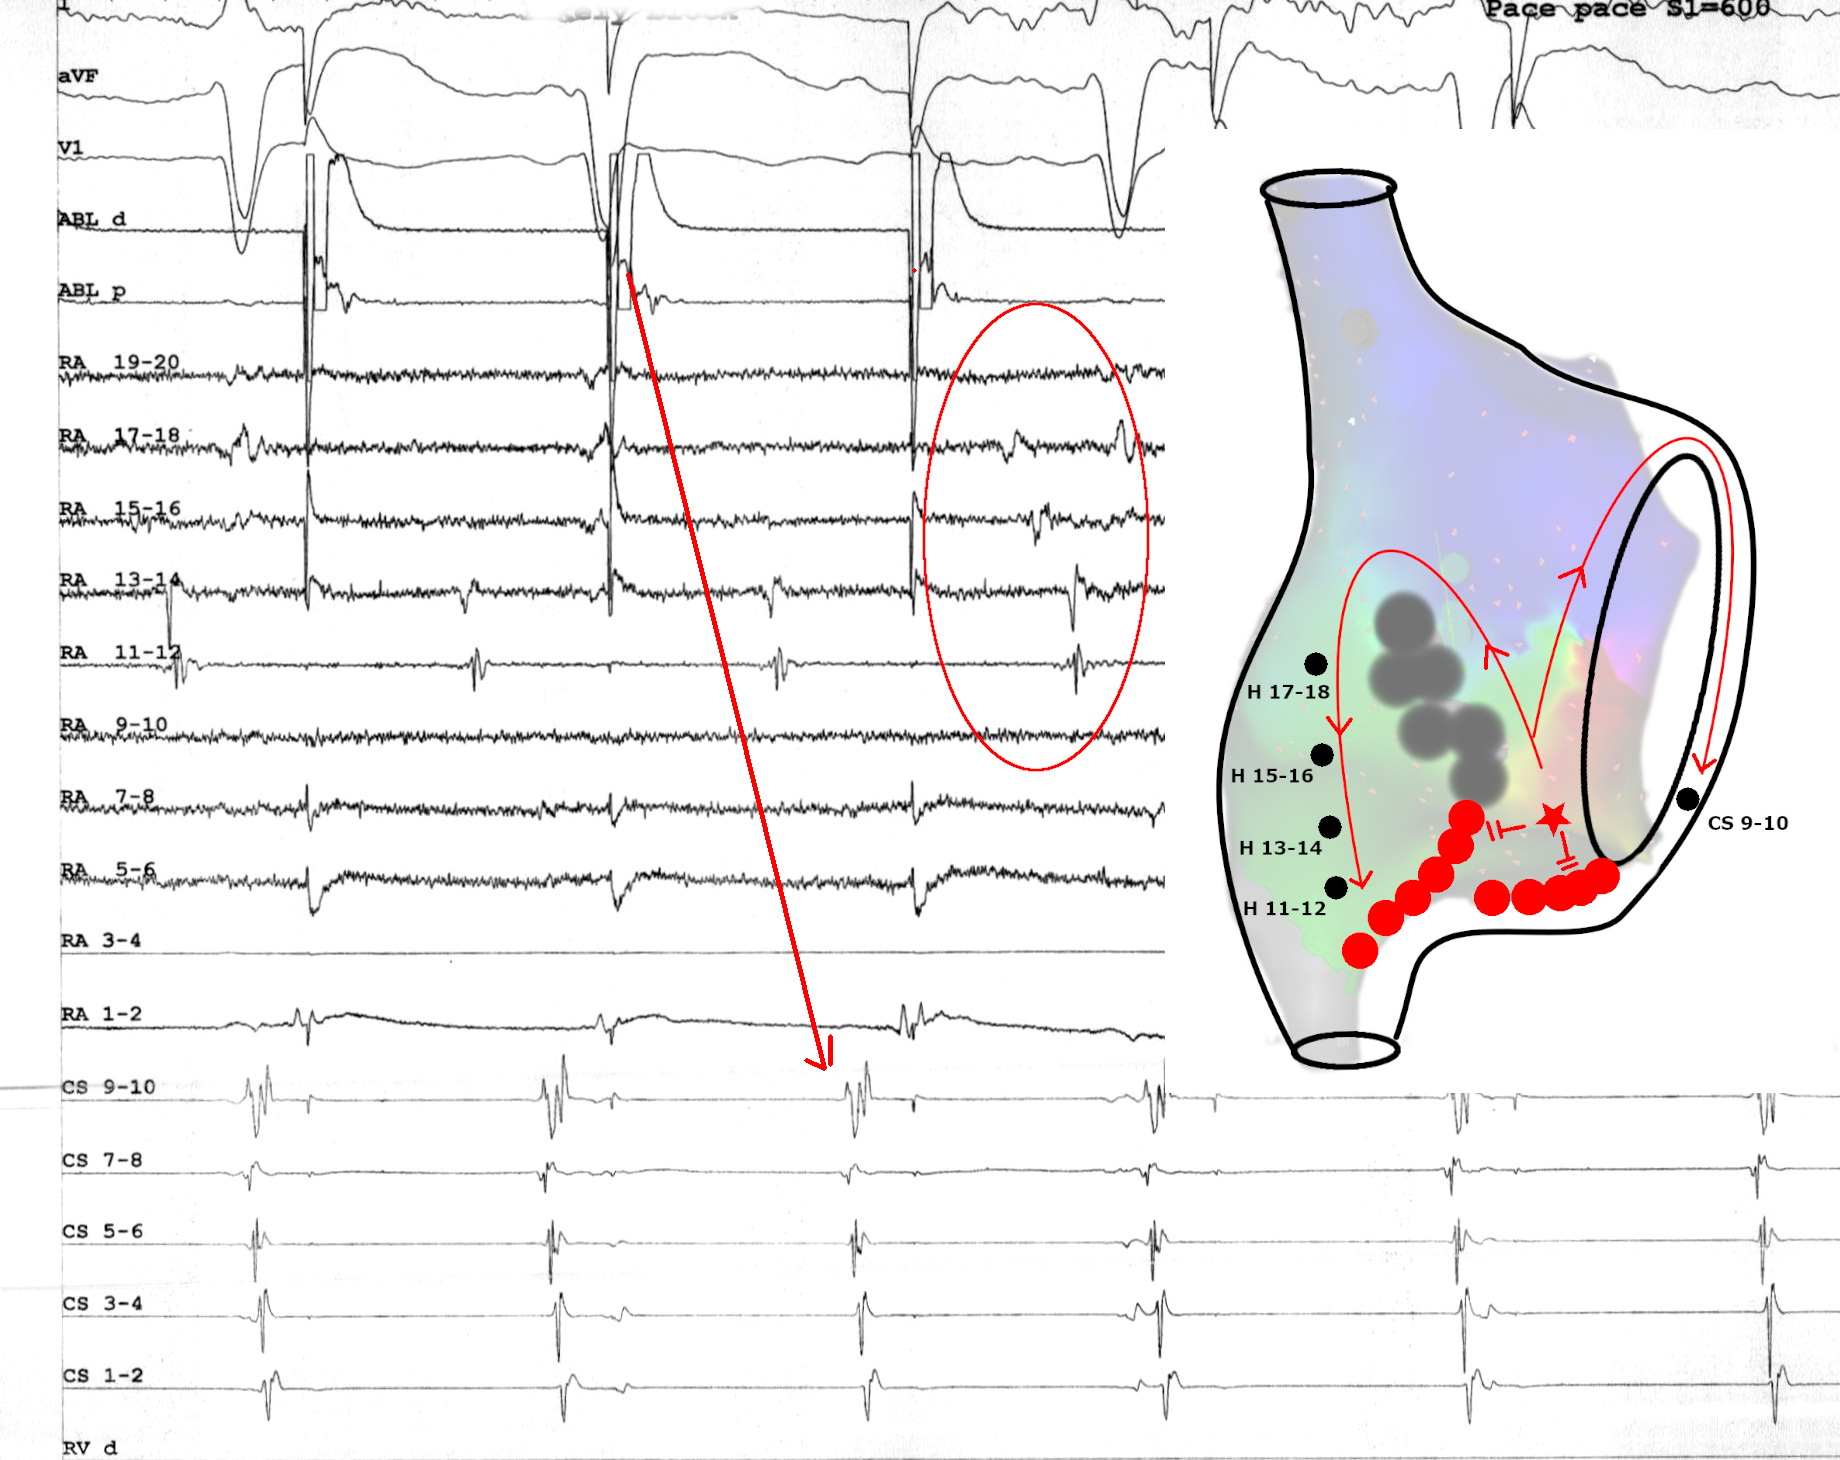

Entrainment

circuits_entrain.JPG

PPI - TCL

circuits_entrain2.JPG

Propagation map